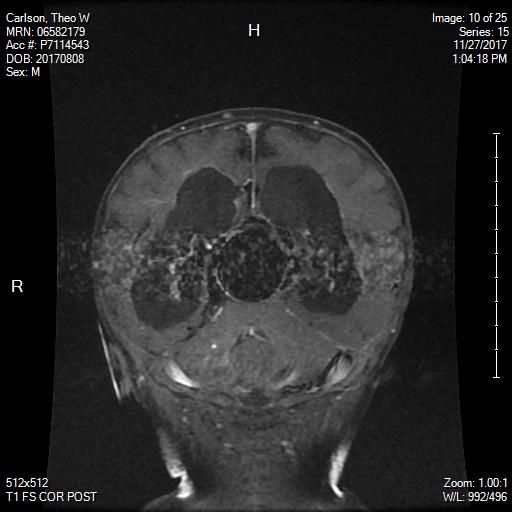

[MRI from 11/27 showing the aneurysm]

Dr. Lin came by to check Theo’s soft spot and to let us know that his ventricles look a little fuller then his 11/27 MRI, but since his soft spot is still soft he will not be recommending a shunt at this time. He cleared Theo to go home but wants to see him every two weeks for a check up.